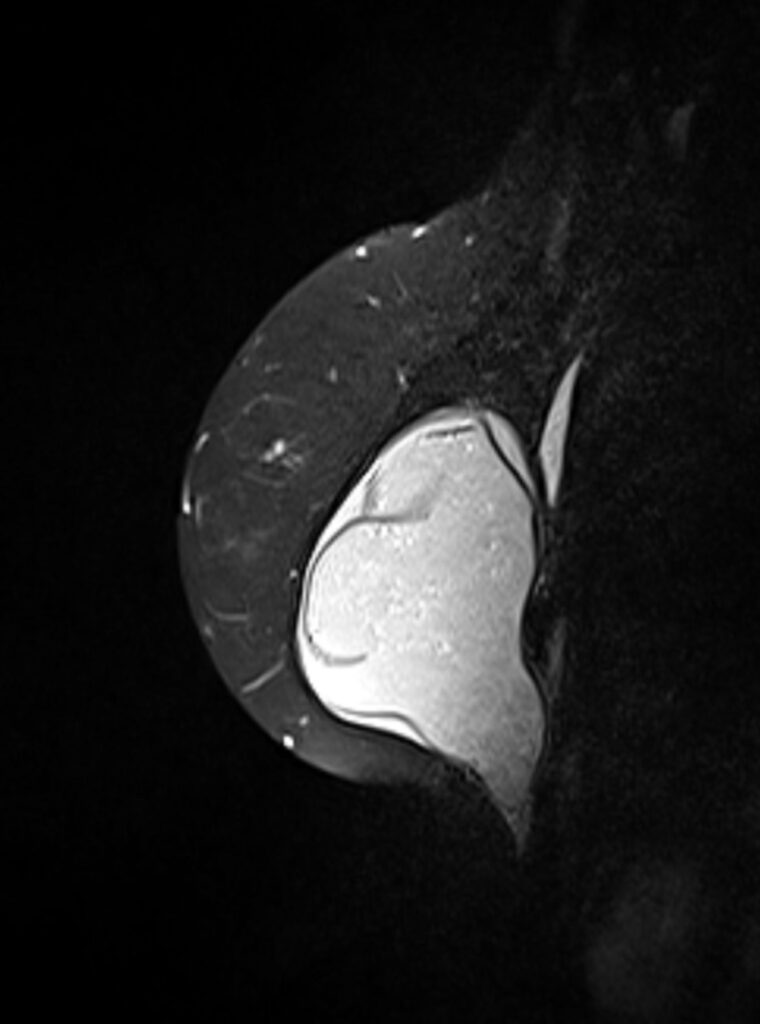

Konnten die klinische Untersuchung, die Mammographie und die Mammasonographie keine eindeutigen Ergebnisse liefern, kann als Ergänzung die Magnetresonanztomographie (MRT) herangezogen werden. Die hohe räumliche Auslösung kann dabei helfen, bereits sehr kleine Herde in der Brust erkennbar zu machen.

Hier zu sehen sind Bilder einer Brust MRT / Mamma MRT.